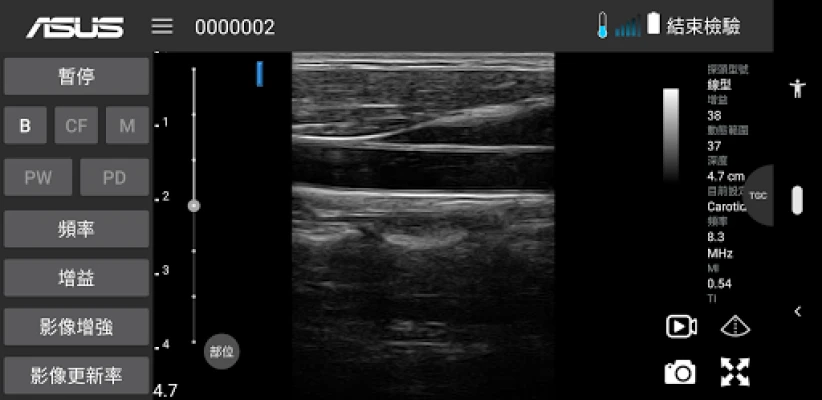

ASUS Portable Ultrasound is a wireless, handheld, pocket-sized imaging tool.

This flexible and feasible APP supports reliable and dependable images for diverse scenarios.